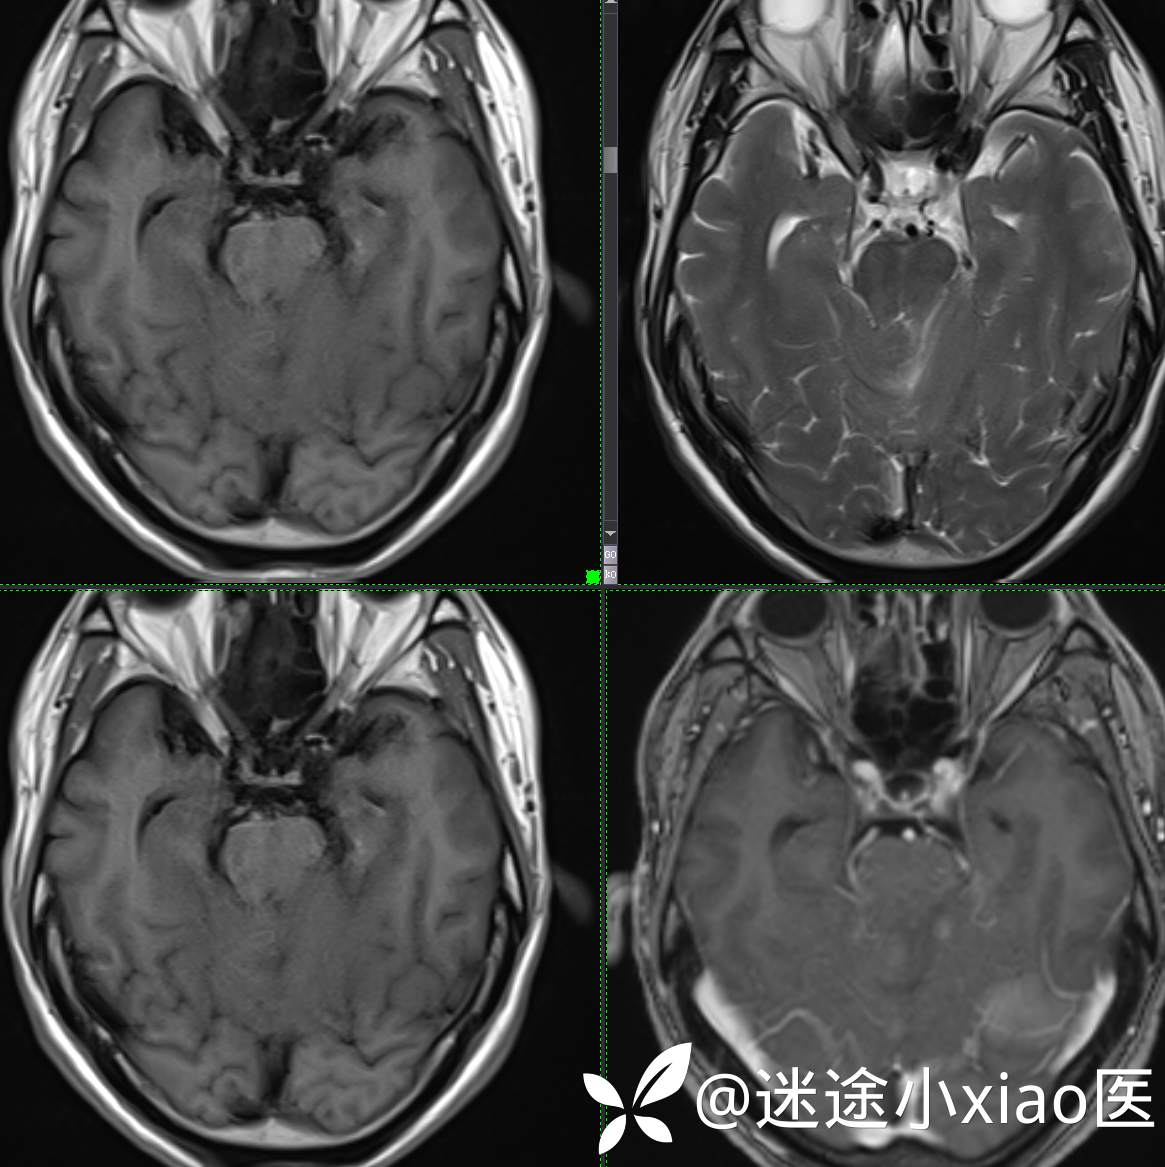

头颈组15:男,62岁,左侧小脑半球占位,原发?转移?是否有意外?

主 诉: 头晕、恶心呕吐半月余。

现病史: 患者半月前无明显诱因下明显头晕,伴恶心呕吐,无意识丧失、无智力明显下降,无视物模糊,无耳鼻腔出血,无四肢抽搐、畸形,无胸闷气促、呼吸困难。

既往:膀胱癌手术史。